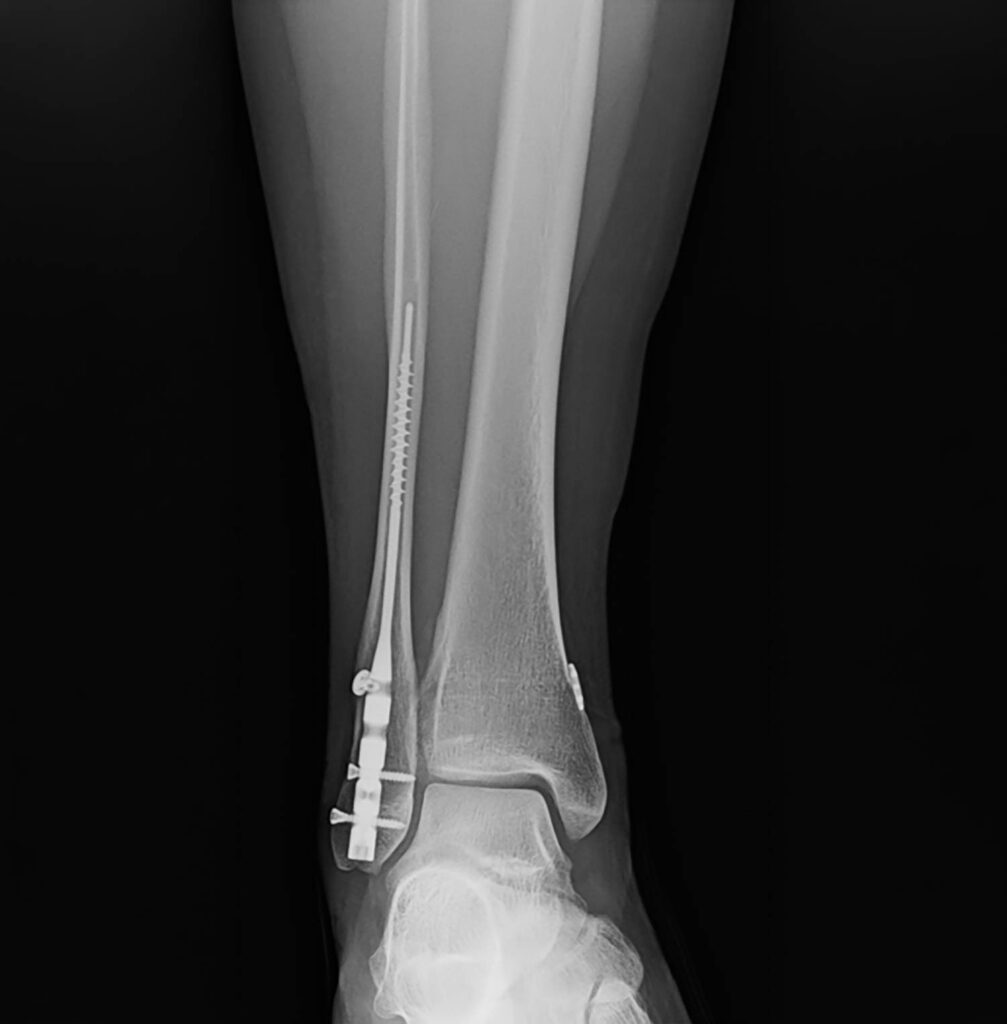

The transition from traditional Open Reduction Internal Fixation (ORIF) with plates and screws toward intramedullary fibular nailing represents a significant paradigm shift in ankle fracture management. While historically reserved for “train wreck” patients–those with compromised soft tissue, diabetes, or advanced age–current clinical evidence suggests that fibular nails are highly effective for simpler fracture patterns, such as stress-positive Weber B fractures.

- Modern Primary Indications: Simple, stress-positive Weber B fibular fractures. These patients benefit from minimally invasive surgery (MIS), zero hardware prominence, and small incisions.

Surgical Technique and Reduction Strategies

A common misconception is that the nail itself achieves the reduction. Experts emphasize that the surgeon must reduce the fracture before or during nail insertion.

- Clamping: Utilize a large, pointed reduction clamp from the medial malleolus to the distal fibula to close the medial clear space. A second percutaneous clamp can be used anterior-to-posterior (A-to-P) to close the fracture site.

- Maintaining Reduction: It is recommended to keep the reduction clamp in place while inserting the nail to prevent the hardware from displacing the fracture or causing shortening.

Radiographic vs. Functional Outcomes

The study utilized the McLennan and Ungersma guidelines to qualify reductions as “good,” “fair,” or “poor.”

- Reduction Accuracy: 97% of cases were reduced to length; 100% achieved closure of the medial clear space.

- Acceptable Displacement: Approximately 9% of cases showed “fair” reduction, often involving a 1–2 mm posterior displacement. This is frequently due to the syndesmotic screw/button passing through the fracture site.

- Clinical Relevance: There is no documented clinical difference in functional outcomes between “good” and “fair” radiographic reductions. Because the fibula is largely extra-articular, a “functional reduction” (restoring gross anatomy, length, and rotation) is sufficient for patient satisfaction and long-term success.